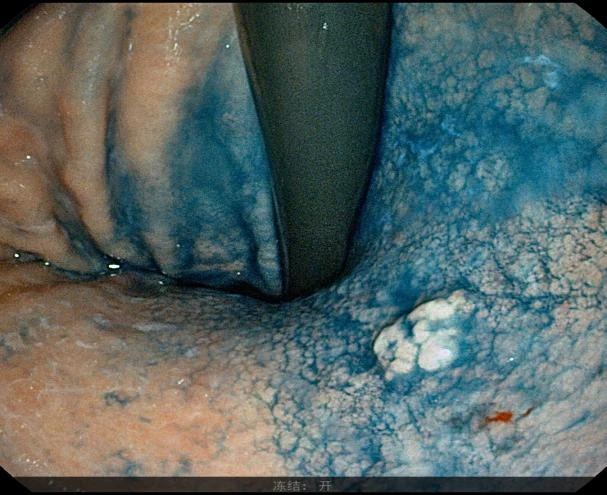

此前,牛女士在我中心进行胃肠镜检查时,郭医生敏锐地发现其胃体中部存在一处约1.2×1.0cm的粗糙黏膜病变。凭借丰富的临床经验,她判断这并非普通炎症。随后的活检病理结果证实了她的担忧:0-IIa型病变,低级别管状腺瘤。这是一枚癌前病变“隐形警报”,若未及时处理,极有可能进展为早期胃癌。